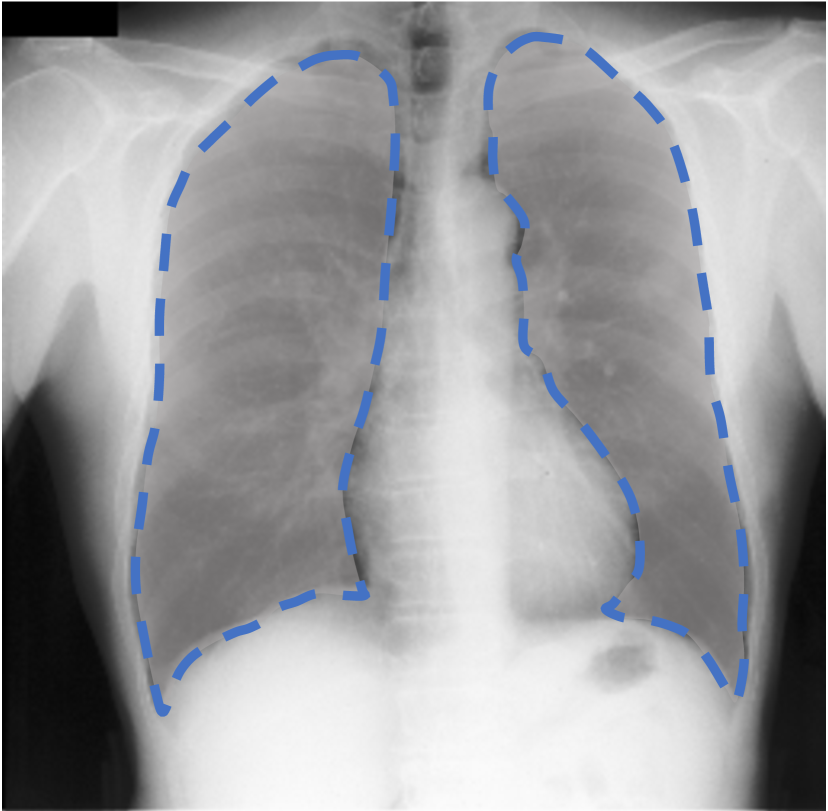

For each of these three datasets, we use three noise settings, denoted by , and . and are two settings synthesized by our Markov process with (expansion) and (shrinkage), respectively. Figure 4 shows examples of our synthesized label noise. We also include the mix of random dilation and erosion noise used by previous work (Zhu et al., 2019; Zhang et al., 2020b; a). This is achieved by randomly dilate or erode a mask with a number of pixels. Note that our Markov label noise can theoretically include this type of noise by setting . Detailed parameters for these settings are provided in the Appendix.

Real-world label noise. To evaluate with real-world label noise is challenging. We are not aware of any public medical image segmentation dataset that has both true labels and noisy labels from human annotators. Therefore, we use a multi-annotator dataset, LIDC-IDRI dataset (Armato III et al., 2015; Armato et al., 2011; Clark et al., 2013), and the coarse segmentation in a vision dataset, Cityscapes (Cordts et al., 2016). The LIDC-IDRI dataset consists of 1018 3D thorax CT scans where four radiologists have annotated multiple lung nodules in each scan. The dataset was annotated by 12 radiologists, and it is not possible to match an annotation to an expert. We use the majority voting as the true labels and the union of four annotations as noisy labels. We process and split the data exactly the same way as Kohl et al. (2018). Cityscapes dataset contains 5000 finely annotated images along with a coarse segmentation by human annotators that we use as the “noisy label”. We only focus on the ‘car’ class because (1) cars are popular objects and are frequently included in images; (2) the coarse annotation of cars is very similar to noisy annotation in medical imaging – they are reasonable distortions of the clean label without changing the topology. See Figure 4(c) for an example. The detailed settings of LIDC-IDRI and Cityscapes can be found in Appendix A.2.1.

Table 1 shows the segmentation results of different methods with synthetic noisy label settings on JSRT , ISIC 2017 and Brats 2020 dataset. Note that QAM cannot be applied to Brats 2020 dataset because their network is designed for 2D only. We compare DICE score (DSC) on testing sets (against the clean labels). For each setting, we train 5 different models, and report the mean DSC and standard deviation. In and , where biases show up in noisy labels, the proposed method outperforms the baselines by a big leap in total case. The compared methods, however, only work when little bias is included, like . is equivalent to setting in our Markov model, resulting in . We also test the proposed method on real-world label noise, results shows in Table 2. Figure 5 shows examples of label correction results. We provide more qualitative results in the Appendix A.4.